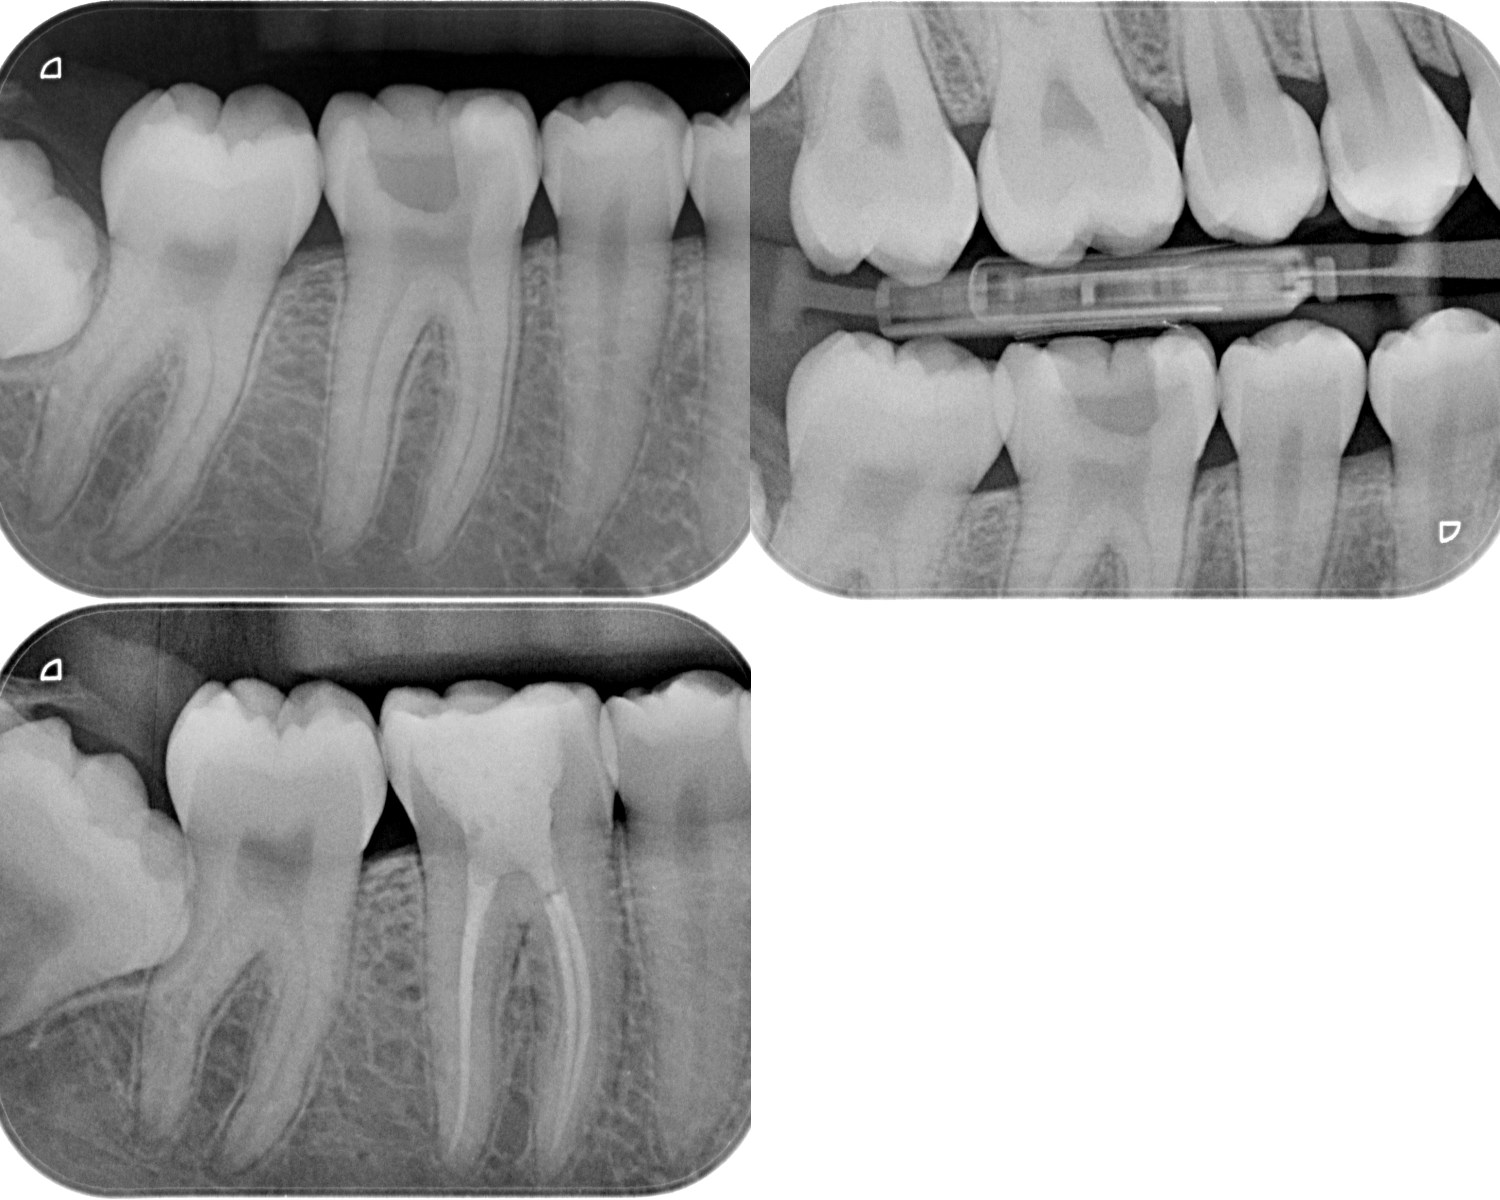

Routine RCT

Revathi Miglani

August 27, 2018

Cases